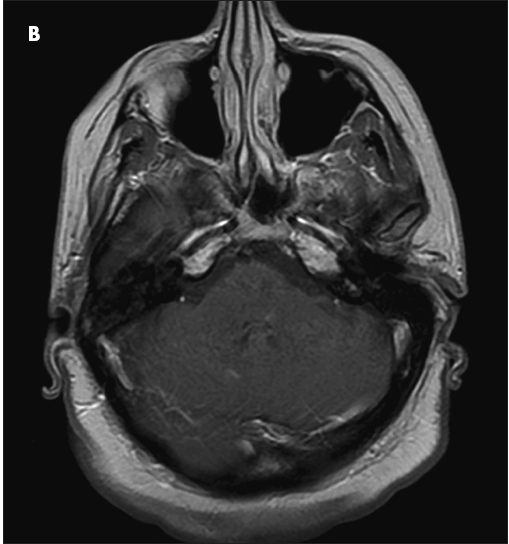

A CT scan of the brain revealed 3 to 4 cm of vasogenic edema in the right posteroinferior parietal-occipital area. Axial T1-weighted (B) and T2-weighted (C) images showed an enhancing lesion in the medial longitudinal fasciculus. A full-body CT scan was negative for malignancy. Lumbar puncture revealed oligoclonal bands in the cerebrospinal fluid; a workup for Lyme disease, Cryptococcus infection, fungal infection, HIV and other viral infections, and bacterial (including acid-fast bacilli) infection yielded negative results.